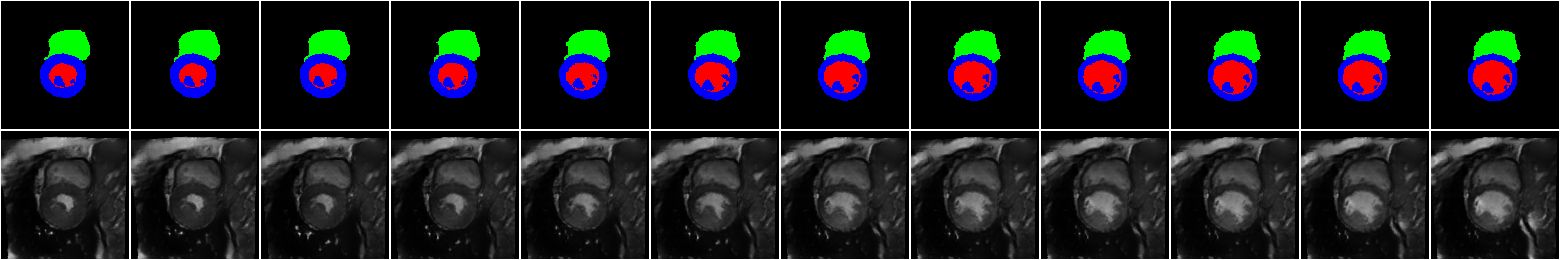

In another experiment, we test our modified VAE setup on the 4D voxelized XCAT labels to show the capability of the method in generating synthetic images in which the global and local styles are matched to images from an unseen dataset. Some sample results are shown in \figurereffig:VAE. The input images of the encoder (representing the style) are depicted in the first column. Two different synthetic images for each style are shown in the second and third columns, and the label maps (the inputs of the SPADE layers) are shown on the top left corner of the resulting synthetic images. In these images the local and global appearance of the style images are transferred to the synthetic images, while keeping the classes of interest intact. This VAE setup provides an additional control on our image generation. The generator is capable of creating realistic heart models, while the encoder transfers the information related to the other surrounding organs. For the sake of comparison, using the same combination of style and label maps, the resulting synthetic images when the IN layers are kept in the style encoder are also shown in the fourth and fifth columns. In these cases, only the global style is transferred and the control on the surrounding regions of the heart is very limited.

fig:VAE